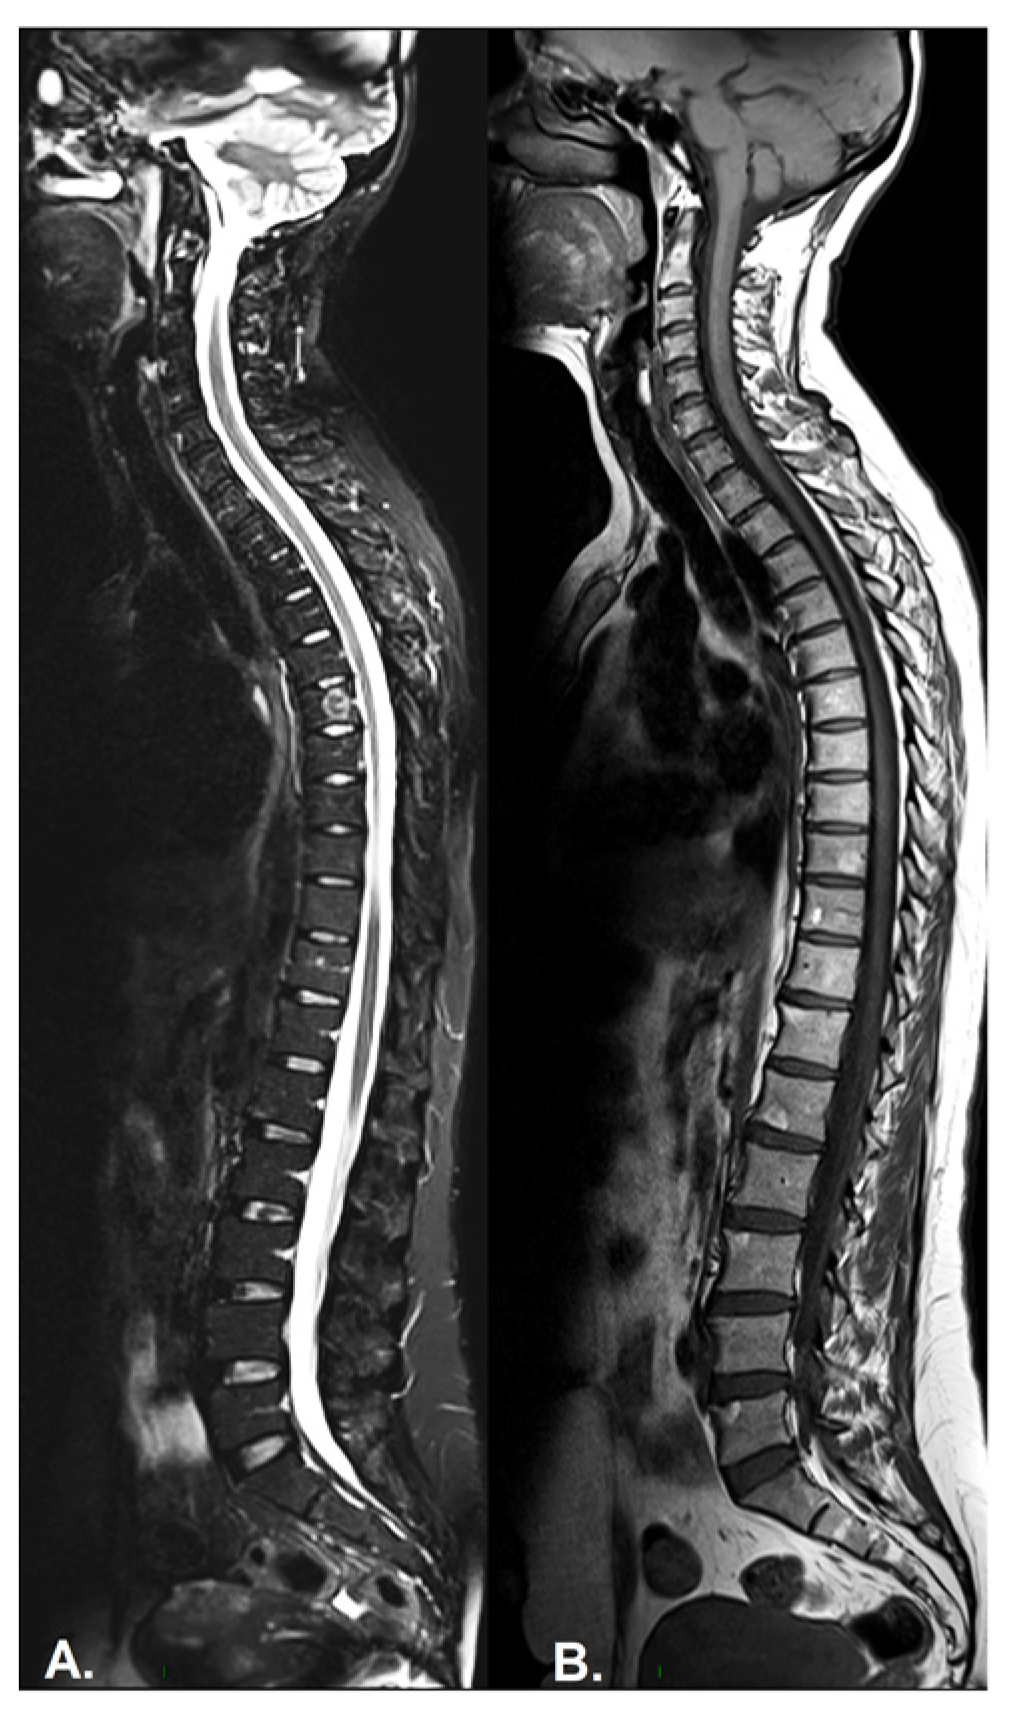

- Inflammation of the vertebral body superior or inferior corners, identified in the early stages as a low signal in T1w, a high signal in T2w and STIR, due to bone marrow edema and later, a high signal in T1w and T2w due to fatty bone marrow degeneration, known as the “shiny corner sign” or “Romanus lesions” (Figure 3). This is also found in ankylosing spondylitis.

- Bulky new bone formation—bone productions in high signal T1w; marginal and paramarginal vertical syndesmophytes distributed asymmetrically along the spine, with a peculiar feature of late PsA, while in SpA, syndesmophytes are typically bilateral and symmetrical, with only a marginal distribution and evolution from caudal to cranial [66]. In axial PsA, syndesmophytes extend towards the adjacent vertebra, while in AS, they are continuous from adjacent vertebra, with a tendency to the formation of osteophytic bridges and further evolution to the bamboo spine [67]. The vertebral joint spaces are preserved until the late stages of the disease.